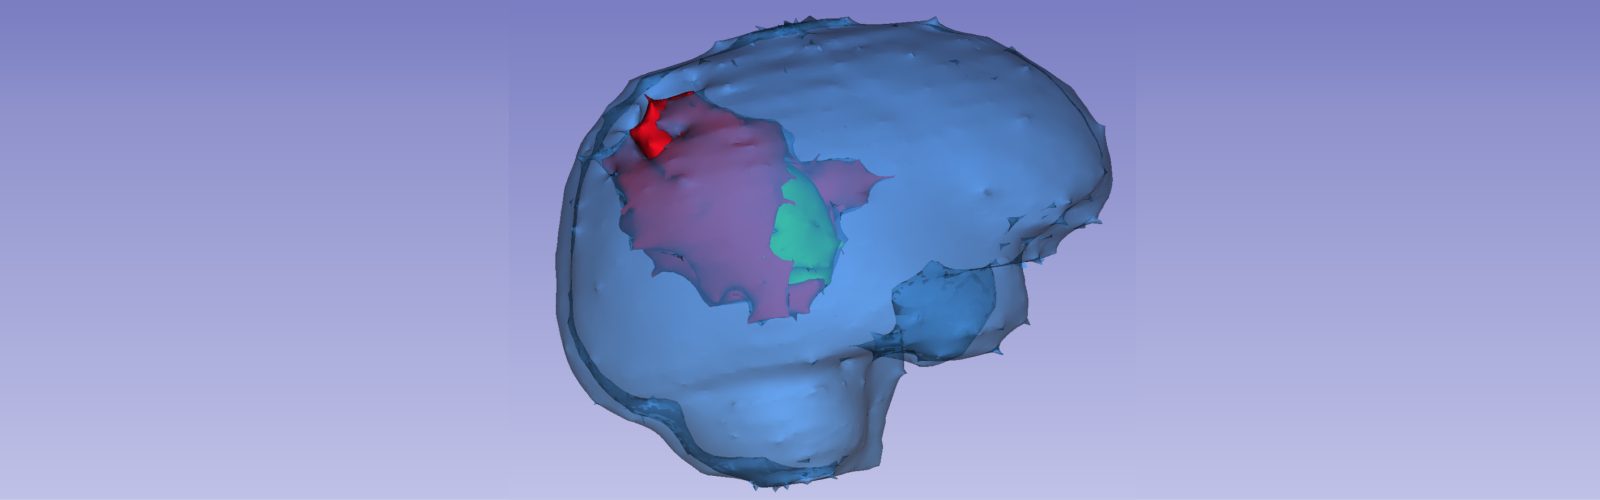

IDiA Lab develops artificial intelligence (AI), machine learning (ML), and statistical modeling approaches for translational applications in oncology and neurological disorders. Our primary focus is on advancing tools for disease prediction, prognosis, and treatment assessment. A key approach of research involves identifying radiomic (image-based) phenotypes from medical imaging and exploring their associations with genomics (radiogenomics) and histopathology (radiopathomics) to enhance disease characterization.